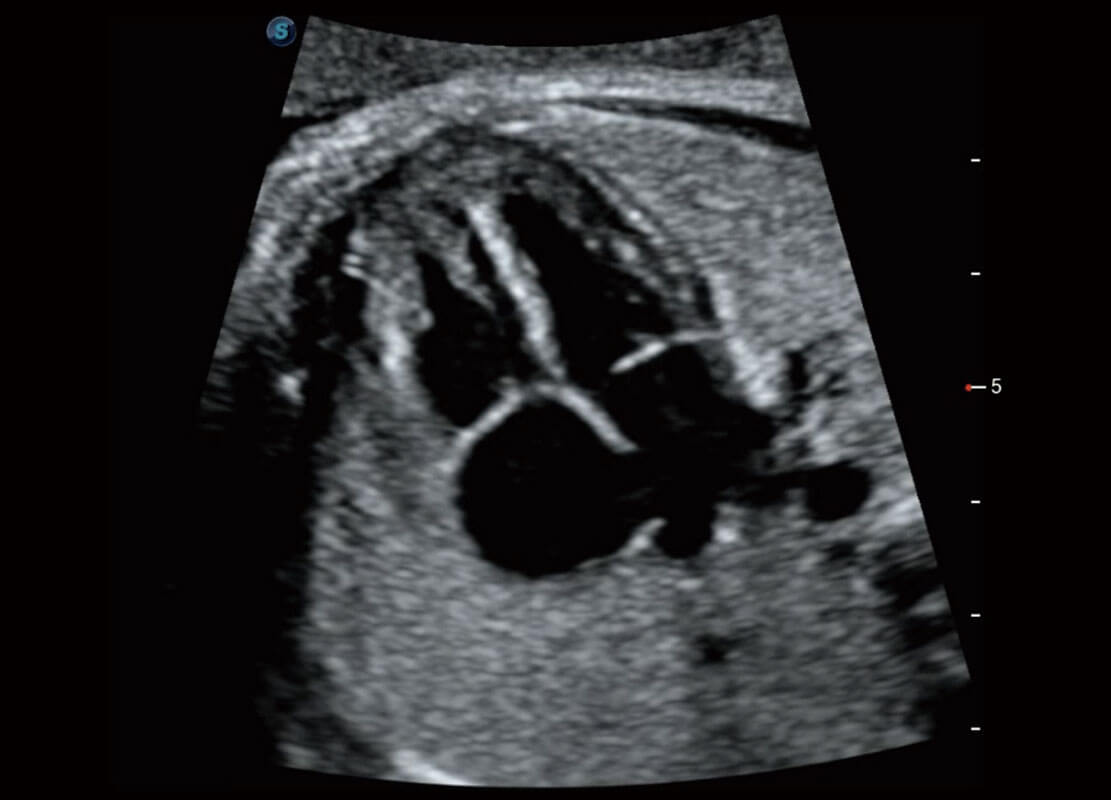

P60优异的图像质量搭载专科探头,在妇科基础疾病的诊断、卵泡生长的监测、输卵管通畅情况的判别等方面为您提供生殖应用方案。

腔内妇科-卵巢